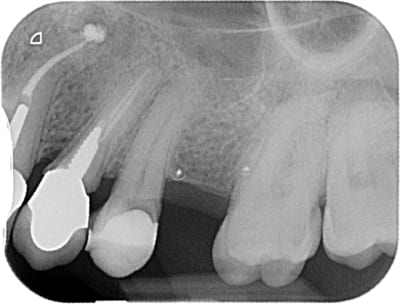

ce patient a une demande essentiellement esthétique,

que me conseilleriez-vous au niveau

des incisives supérieures ?

11 et 21 sont vitales.

pour le haut je ne suis pas sur que la forme de la 12 soit très esthétique,

ainsi est-ce que refaire la 12 et cc pour 22 21 11 parait pertinent ?

sauf que si on refait 12 en gardant l'inlay-core ( je suis toujours prudent avec les déposes !!), cela vaut-il le coup de faire des cc ?